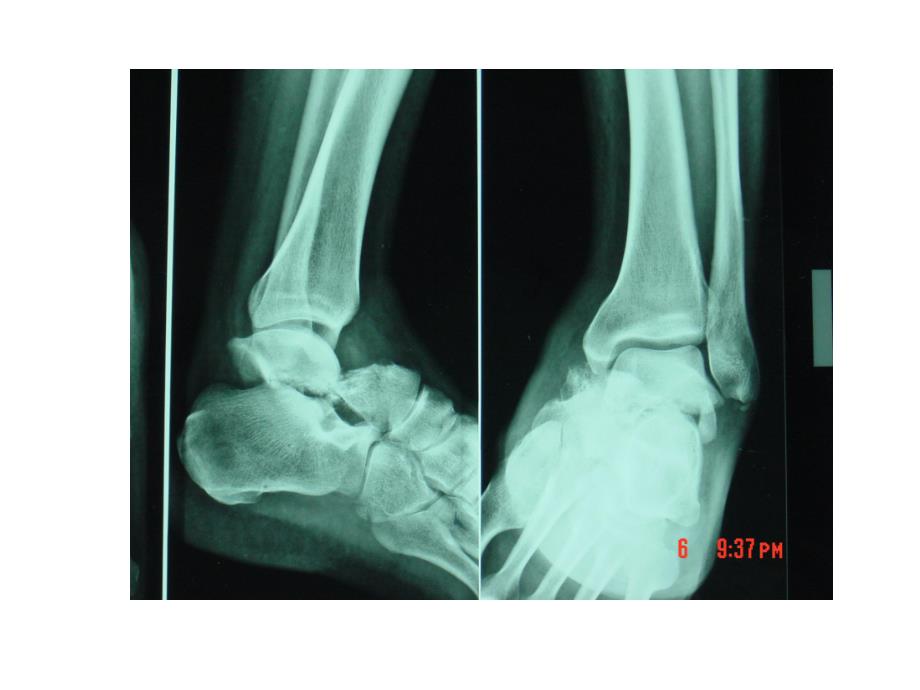

1、距骨骨折Diagnosis TypeFractureDislocation颈骨颈骨折的Hawkins分型分型分型骨折特征骨折特征骨坏死率骨坏死率I型无移位的距骨颈骨折小于10%II型移位的距骨颈骨折合并距下关节的脱位或半脱位40%III型移位的距骨颈骨折合并踝关节和距下关节的脱位90%IV型距骨颈骨折移位,距骨体从踝关节和距下关节中脱出,距舟关节的半脱位几乎100%骨折部位骨折部位脱位脱位分型分型距骨骨折距骨头骨折距骨颈骨折距骨体骨折解剖距骨头骨折 骨折线累及距骨头关节面,影响距舟关节稳定 典型的距骨头骨折为复合性损伤,常并发距舟关节半脱位距骨颈骨折与距骨体骨折 Inokuchi等认为距骨体垂

2、直骨折的下方骨折线位于距骨外侧突以前为距骨颈骨折,位于外侧突以后为距骨体骨折Dislocation距骨脱位距骨周围脱位距下关节距骨全脱位距下关节踝关节距骨周围脱位 距骨周围脱位:又称距骨下脱位或距跟舟状骨脱位。一般包含距跟关节和距舟关节同时脱位,但踝关节和跟骰关节保持正常。大约有10%的内侧脱位和20%的外侧脱位不能闭合复位。解剖结构的嵌顿限制常常使闭合复位不能完成。闭合复位不宜反复进行,以免加重关节软骨的损伤及骨折移位更加显著距骨周围脱位距骨周围脱位 切开复位内固定或小骨折块切除会降低关节退变的发生。切实开复位的指征有:开放性脱位;闭合复位失败;并发明显骨折;肿胀明显,脱位的距骨头压迫皮肤,

3、可能导致皮肤坏死;伴随其他部位损伤距骨全脱位 距骨全脱位:距骨从踝关节、距下关节脱位,常常伴有距舟关节脱位 由高能量损伤所致,应尽快复位 手术治疗时应根据距骨脱位的方向和部位,可采用前内侧或前外侧切口,也可以两者联合应用 如果距骨复位后仍然不稳定,可行距下关节、距舟关节克氏针固定。Type距骨颈骨折的分类距骨颈骨折分类:Hawkins-Canale分型,基于骨折的移位和脱位程度进行分类,能很好地预测距骨缺血性坏死的发生率,但对于骨折的粉碎程度未加以重视目前常用的分类系统为Hawkins于1970年提出,1978年Canale和Kelly提出距骨颈骨折的IV型分型分型骨折特征骨折特征骨坏死率骨坏

4、死率I型无移位的距骨颈骨折小于10%II型移位的距骨颈骨折合并距下关节的脱位或半脱位40%III型移位的距骨颈骨折合并踝关节和距下关节的脱位90%IV型距骨颈骨折移位,距骨体从踝关节和距下关节中脱出,距舟关节的半脱位几乎100%距骨颈骨折的Hawkins分型II型III型骨折(正侧位)III型骨折距骨颈骨折分型距骨体骨折 Sneppen等把距骨体骨折分为6型 I型:距骨滑车的压缩骨折,仅累及滑车的内侧或外侧,不包括内外踝部分 II型:冠状面的剪切力骨折,该型骨折易与距骨颈骨折混淆,但骨折线更靠后,累及距骨滑车,影响踝关节背屈;III型:矢状面的剪切力骨折 II型与III型:两种剪切力骨折一般均

5、累及踝关节和距下关节 IV型:距骨后突骨折 V型:距骨外侧突骨折 VI型:距骨体粉碎性骨折,踝关节和距下关节严重失稳概述 临床上距骨骨折约占全身骨折的1%解剖特殊,治疗极具挑战性 距骨骨折治疗不当畸形愈合缺血性坏死创伤性关节炎(踝关节、距下关节)关节不稳定距骨颈骨折为什么容易出现坏死距骨颈骨折为什么容易出现坏死解剖 距骨骨外血管系统包括胫后动脉(跗骨管动脉、三角动脉支、后结节动脉)、足背动脉(颈上动脉)及腓动脉(跗骨窦动脉)整个距骨以距骨头血运最丰富,距骨体的前部及外侧面是血供的薄弱环节,仅通过增厚的韧带与关节囊分布于距骨供应其血运,骨折损伤任一血管环均易造成距骨体发生坏死。距骨血供【6】解剖